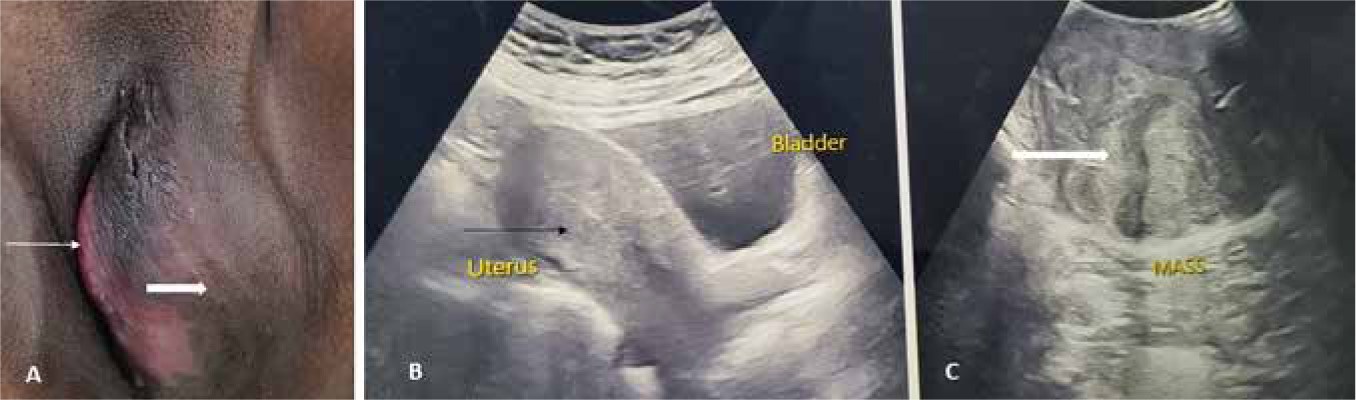

A 41-year-old multiparous woman presented with mass in the perineum of one year duration and discomfort in a sitting position since a month previously. There was no history of fever, local pain, pruritus vulvae, or discharge from the mass. Her bowel and bladder habits were normal. Her menstrual cycles were regular, with average flow, no dysmenorrhoea, and her last menstrual period was 18 days ago. She was para 2 with previous uneventful vaginal deliveries. Her last childbirth was 18 years previously, and she had been sterilised. Her history was uneventful and there was no family history of gynaecological malignancies or tumours. On examination, she was conscious, co-operative, and afebrile. Her pulse rate was 86/minute and blood pressure was 140/90 mm Hg. General and abdominal examination was unremarkable. On examination of the vulva, there was a mass of size 10 × 8 cm on the left side, involving the labium majus and minus, distorting the introitus, which was firm in consistency, with a small pus point on the muco-cutaneous junction (Fig. 1 A). On per speculum examination, the cervical os was obscured due to the mass. Per vaginal examination revealed the uterus to be anteverted, normal size, firm, mobile, with bilateral fornices free. A provisional diagnosis of Bartholin’s cyst was made, and she was further worked up.

Fig. 1

Preoperative images. (A) Vulval mass of size 10 × 8 cm on the left side, involving the labium majus (thick white arrow) and minus, distorting the introitus (thin white arrow). (B) Preoperative pelvic ultrasound showing a normal uterus (thin black arrow). (C) Transperineal ultrasound showing a solid lobulated mass with heterogenous echotexture (thick white arrow), suggestive of vulval fibroid

Her haemoglobin was 10.7 g/dl, total leucocyte count 10.07 × 103/cumm, and liver and kidney function tests were within normal limits. Pelvic ultrasound was done, which showed a normal sized uterus and ovaries (Fig. 1 B). As the vulval mass was firm in consistency, transperineal ultrasound was performed, which revealed a solid lobulated mass with heterogenous echotexture, measuring 10 × 8 cm, with mild vascularity, in the left vulval region (Fig. 1 C). A preoperative diagnosis of vulval leiomyoma was made, and she was planned for excision under antibiotic cover.